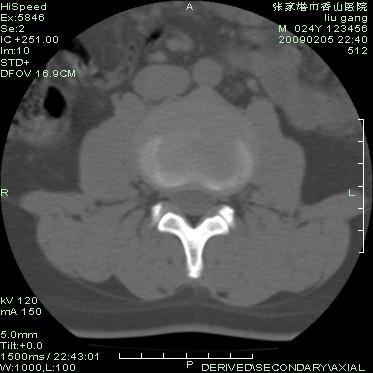

以下是引用随光逐影在2009-3-11 14:43:00的发言:[br]平片:l3、4、5及s1前上缘见类似“切角征”。[br]ct扫描:腰椎多个节段椎间盘向椎体内(椎体前部)突出。